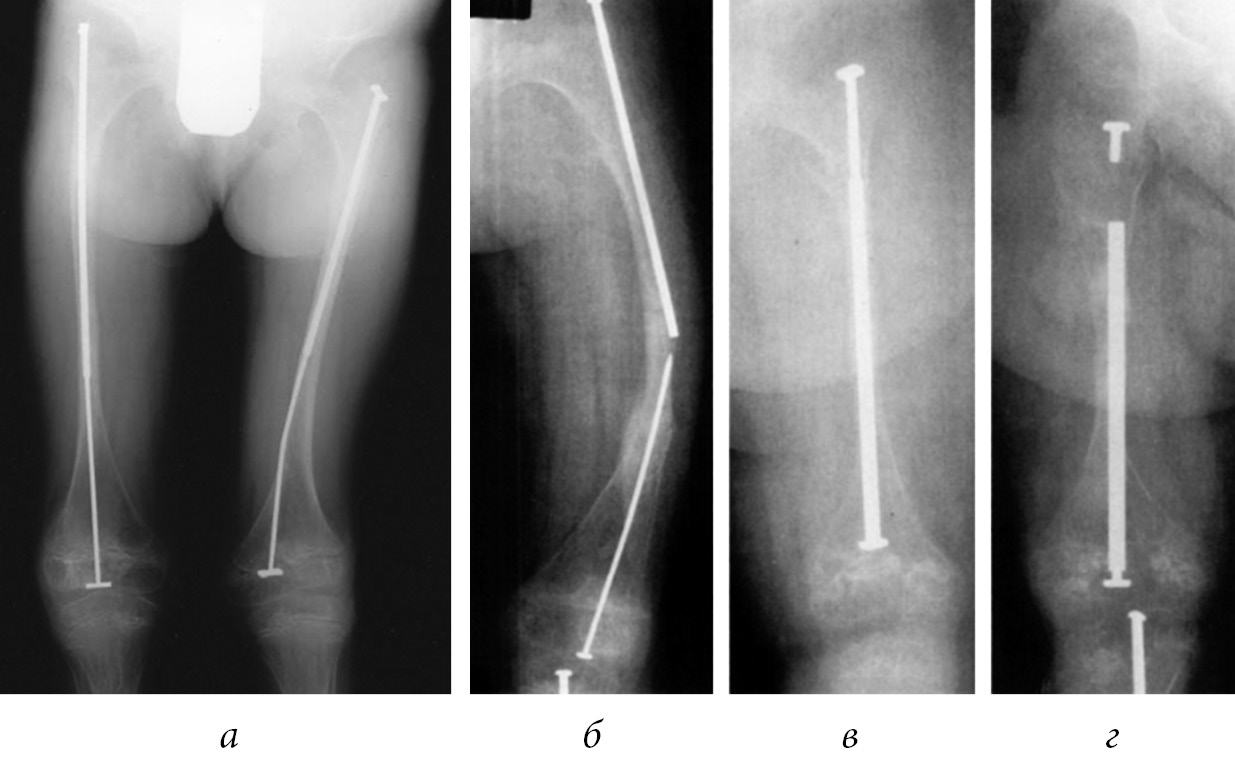

Soft tissues play a key role in the formation of arcuate deformations of long tubular bones. The flexor muscles prevent the bone growth that results in deformity. This is due to the popliteal flexor in the femoral region that leads to anterolateral bending of the bone. This function is performed by the gastrocnemius and fibular muscles in the leg region that cause anteromedial curvature (Fig. 3). Deformed lower limbs lose their biomechanical strength, resulting in increased strain in the deformation apex area that leads to deformation progression and fracture at its height. The purpose of congenital and post-traumatic deformities correction is to reduce the frequency of fractures and ensure the proper growth of the bone to verticalize the child and teach him to walk.

Fig. 3. Deformations of the lower extremities with osteogenesis imperfecta

The basic principle of surgical treatment is restoring limb anatomy and intramedullary splinting at the maximum extent of the bone. The literature describes using the following structures for fixing bone fragments: non-telescopic (Rush nail, Kuntscher’s pin), titanium elastic nails (TEN), Kirchner pins, unreamed humeral nails, telescopic internal fixation devices (Bailey–Dubow, Sheffield, Fassier–Duval rods), plates, and external fixation devices.